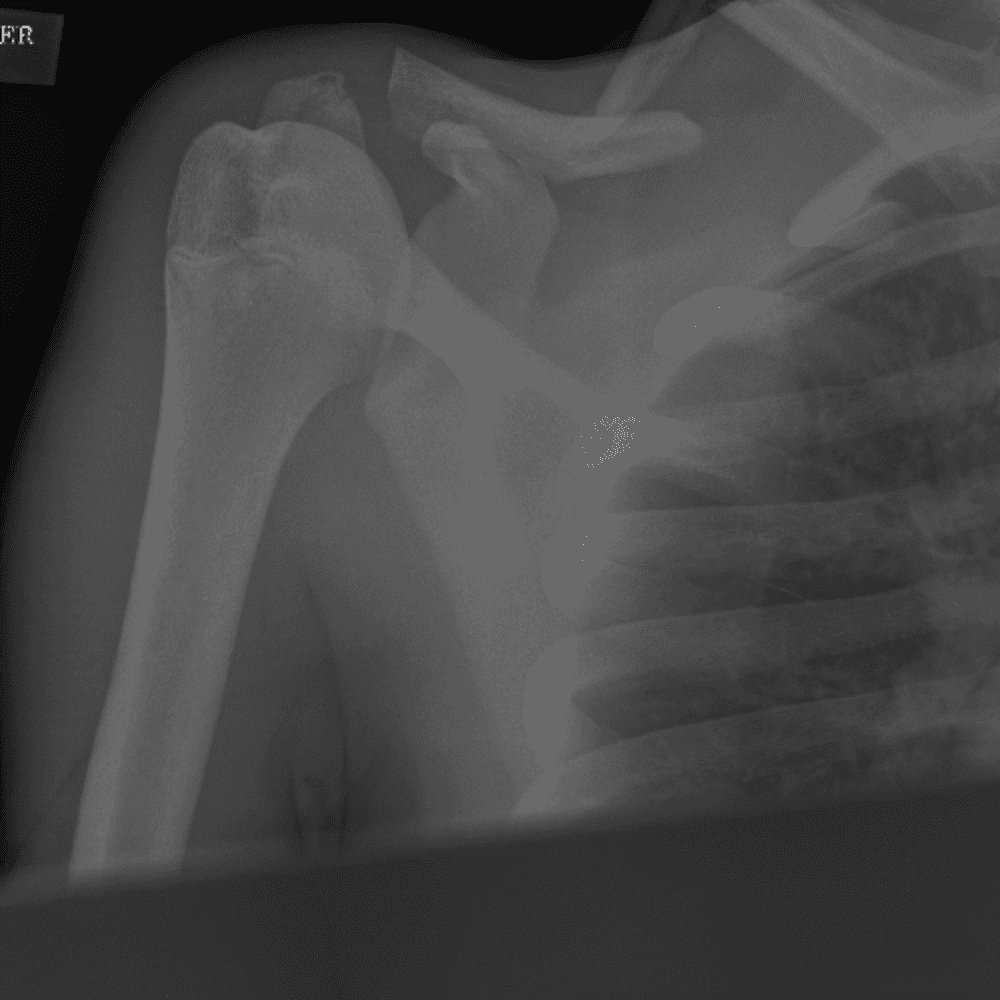

Simuliert den Dienst durch subtile oder schwierige Fälle und einige Normalbefunde.

30 Fälle